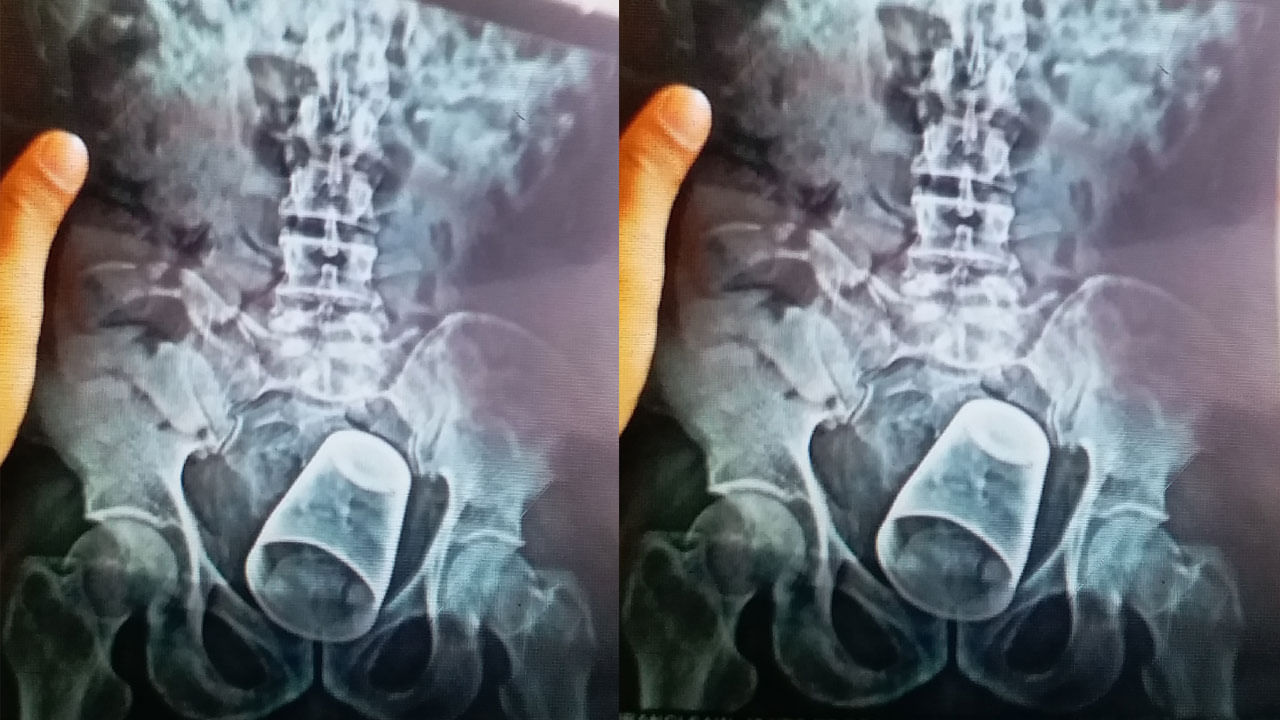

Bihar: బిహార్లోని నవాదా జిల్లా(Nawada District)లో షాకింగ్ ఇన్సిడెంట్ వెలుగుచూసింది. ఓ వ్యక్తి మలద్వారంలోకి.. స్టీల్ గ్లాస్ చొచ్చుకెళ్లింది. దీంతో అతడు నొప్పితో విలవిల్లాడిపోయాడు. వెంటనే ఫ్యామిలీ మెంబర్స్ అతడిని పాట్నా(Patna)లోని పీఎంసీహెచ్ ఆస్పత్రికి తరలించారు. తొలుత కేసు వివరాలు తెలుసుకుని డాక్టర్లు స్టన్ అయ్యారు. ఆపై పరీక్షలు చేసిన డాక్టర్లు.. మలద్వారం నుంచి గ్లాసును వెనక్కి తీయడం సాధ్యం కాదని నిర్ధారించుకున్నారు. ఎక్స్రే ద్వారా స్టీల్ గ్లాసు.. బాధితుడి మలద్వారంలో చాలా లోతుకు వెళ్లిందని గుర్తించారు. ఆపై డాక్టర్ వినయ్ కుమార్ నేతృత్వంలోని ఐదుగురు సభ్యుల వైద్య బృందం విజయవంతంగా ఆపరేషన్ నిర్వహించింది. పొట్టకు ఆపరేషన్ నిర్వహించి గ్లాసును బయటకు తీశారు డాక్టర్లు. ఆపరేషన్ పూర్తైన తర్వాత బాధితుడిని అబ్జర్వేషన్లో ఉంచారు. అతడి పరిస్థితి బాగానే ఉండటంతో కొద్ది గంటల తర్వాత జనరల్ వార్డుకు షిఫ్ట్ చేశారు. గ్లాసు అతడి రహస్య భాగంలోకి ఎలా వెళ్లిందన్న విషయంపై డాక్టర్లు అనుమానం వ్యక్తం చేస్తున్నారు. బాధితుడికి మతిస్థిమితం సరిగా లేదని బంధువులు చెబుతున్నప్పటికీ.. అతడు తమతో మాములు వ్యక్తిలానే ప్రవర్తించాడని వైద్యులు తెలిపారు. స్టీల్ గ్లాసును బోర్లా వేసి.. దానిపై కూర్చున్నట్టు అతడు చెప్పినట్లు వెల్లడించారు. వైద్యులు ఈ విషయంపై పలు అనుమానాలు వ్యక్తం చేశారు. తాంత్రిక పూజలను సాధన చేసేందుకే అతను గ్లాస్పై కూర్చొని ఉంటాడని అనుమానిస్తున్నారు.